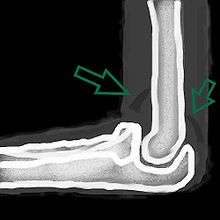

| A traumatic right knee effusion. Note the swelling lateral to the kneecap as marked by the arrow. | |